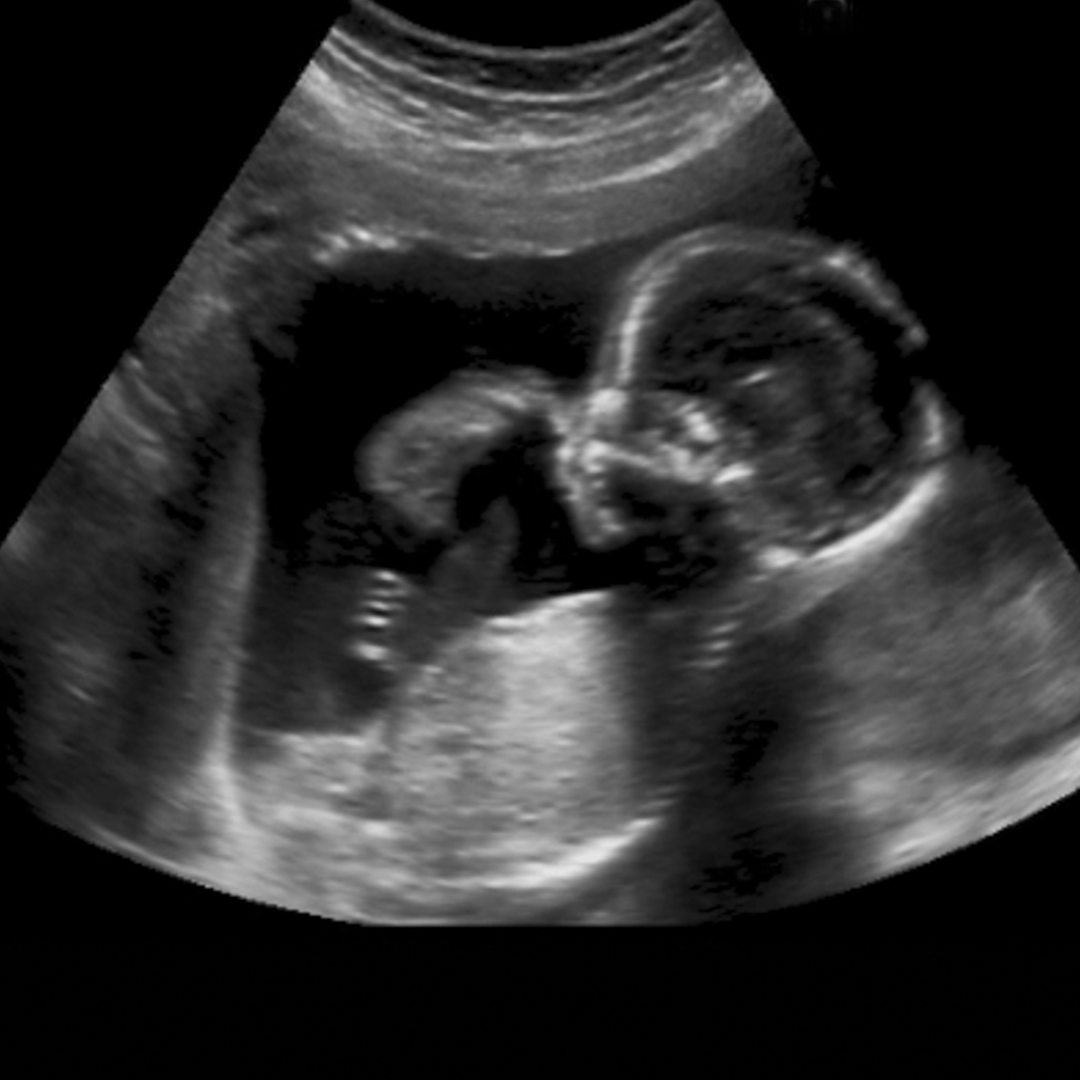

בהיריון הזה, החליטו שבשבוע 13 יבצעו קשירה של צוואר הרחם וכך היה. עברנו יד ביד את ההיריון. התמודדנו יחד עם הפחדים והרגשות שעלו וצפו והם בהחלט באו. עברנו יום אחרי יום, שבוע אחרי שבוע, חודש אחרי חודש עד שהגענו לשבוע 27 בו היא נכנסה לשמירת היריון. והיא שמרה. כמה שהיא שמרה על ההיריון היקר הזה.

כשהוציאו לה את הקשירה בשבוע 37, הייתה בטוחה שהיא יולדת תוך רגע אבל הגוף שלה, זה שהיא לא בטחה בו, ידע את העבודה שלו. ידע שהוא צריך לשמור! והוא שמר!! היא חזרה אלי בשבוע 40 לטיפולי השראת לידה, דרך הרפלקסולוגיה

יום אחרי הקסם נולד